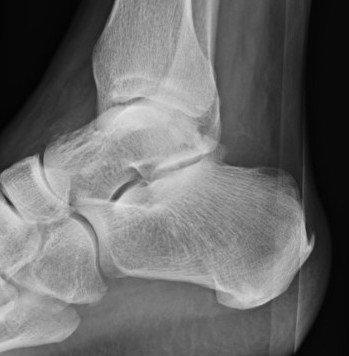

Fracture of the posteromedial / posterolateral process

- forced plantar flexion - impingement especially ballet / soccer

- excessive dorsiflexion - increased tension on PTFL with avulsion

Fracture of the posterior process involving the subtalar joint

- seen after subtalar dislocations